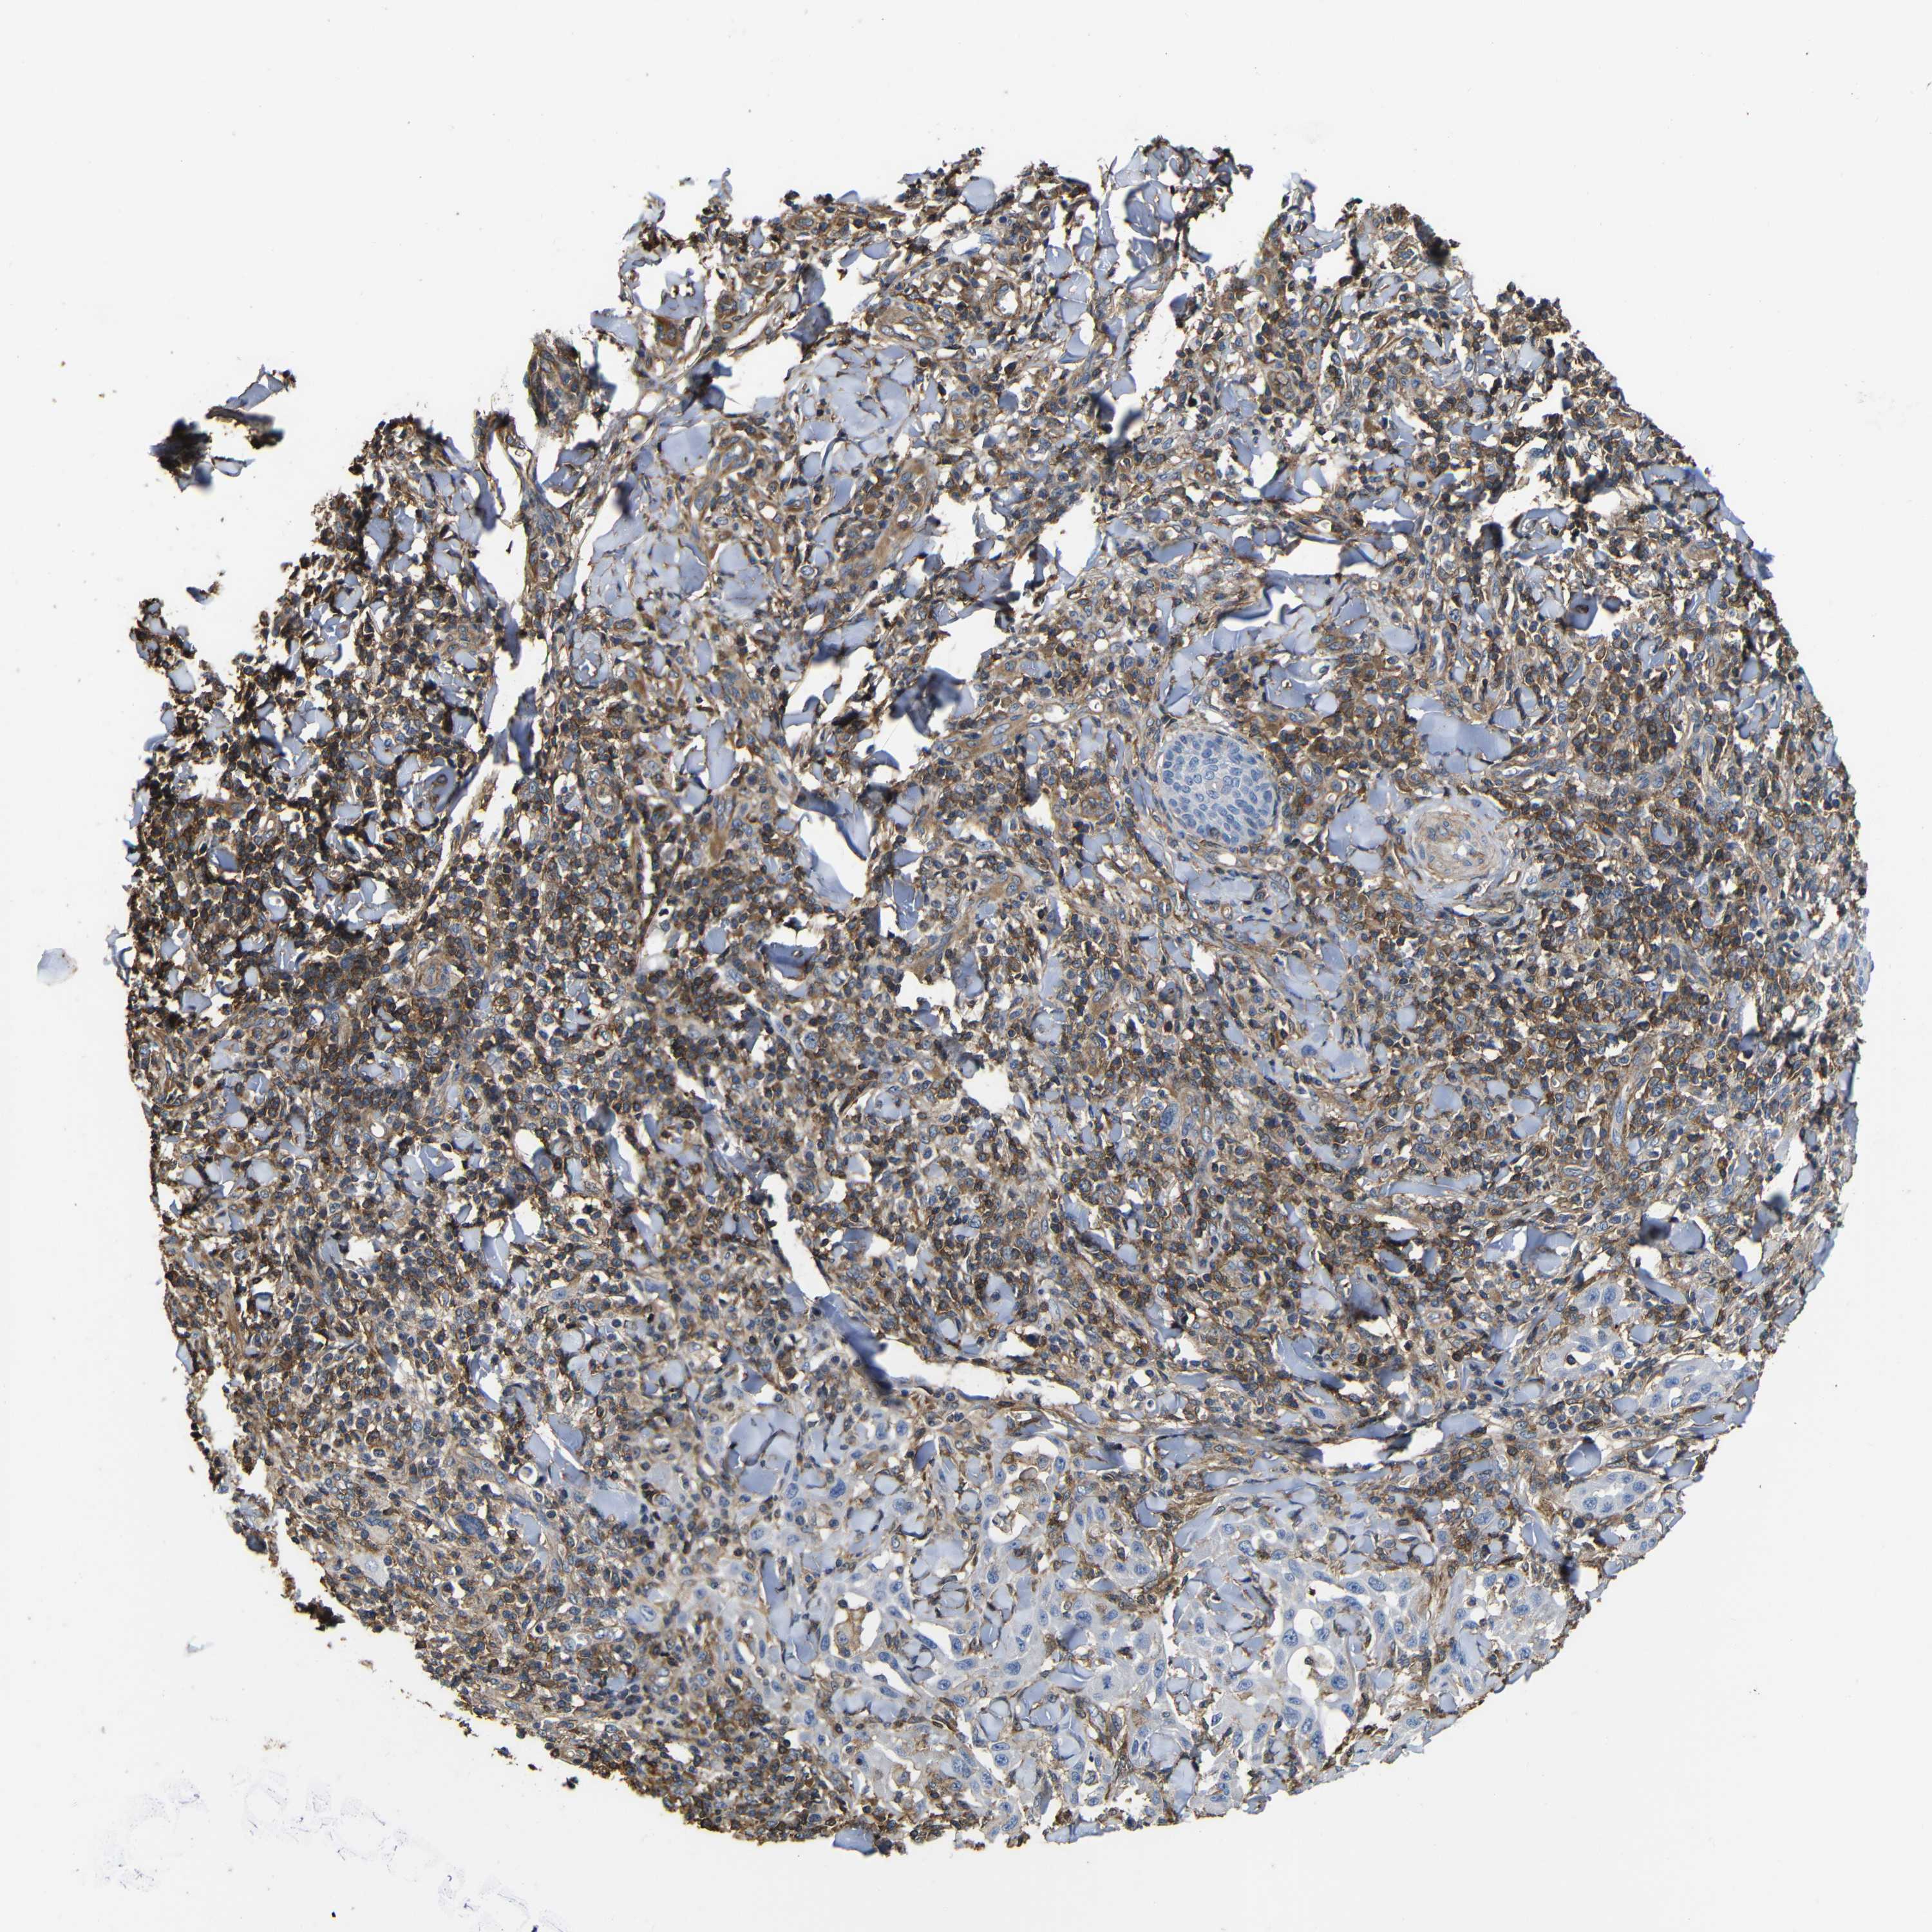

SKIN CANCER - Protein expressioni

A mouse-over function shows sample information and annotation data. Click on an image to view it in a full screen mode. Samples can be filtered based on level of antibody staining by selecting one or several of the following categories: high, medium, low and not detected. The assay and annotation is described here.

Each image is clickable and will lead to virtual microscopy that enables deeper exploration of all samples and also displays staining intensity scores, fraction scores and subcellular localization as well as patient and tissue information for each sample.

Antibody CAB009092

Staining

High

Intensity

Strong

Quantity

>75%

Location

Nuclear

Squamous cell carcinoma, NOS